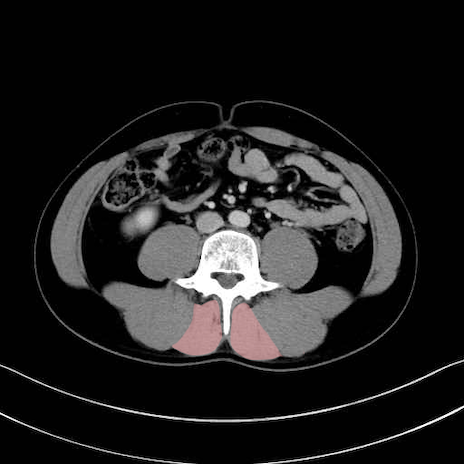

多裂筋 (Multifidus)